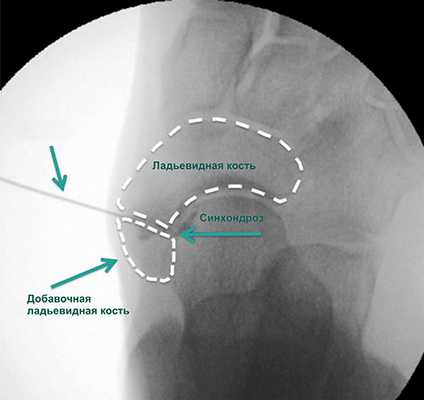

Введение в области синхондроза ладьевидной кости лекарственных препаратов при острых воспалительных явлениях в этой области осуществляется под лучевым контролем и в условиях кратковременной общей анестезии. Оно помогает подтвердить диагноз и купировать воспалительные явления.

Правильность положения иглы подтверждается введением рентгенконтрастного препарата